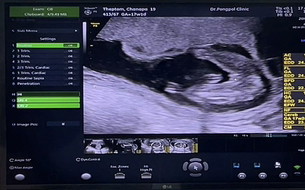

คุณหมอบอกน้องเป็นผู้หญิง แม่ๆช่วยคอนเฟิร์มหน่อยค่ะ ❤️#ขอบคุณสำหรับคำคอมเม้นล่วงหน้าค่ะ

ผู้หญิง100% ค่ะแบบนี้

หญิงค่ะแม่ ชัดเลย